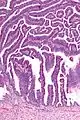

| Micrograph of a villoglandular adenocarcinoma the cervix. H&E stain. | |

The name of the lesion describes it microscopic appearance. It has nipple-like structures with fibrovascular cores (papillae) that are long in relation to their width (villus-like), which are covered with a glandular pseudostratified columnar epithelium.